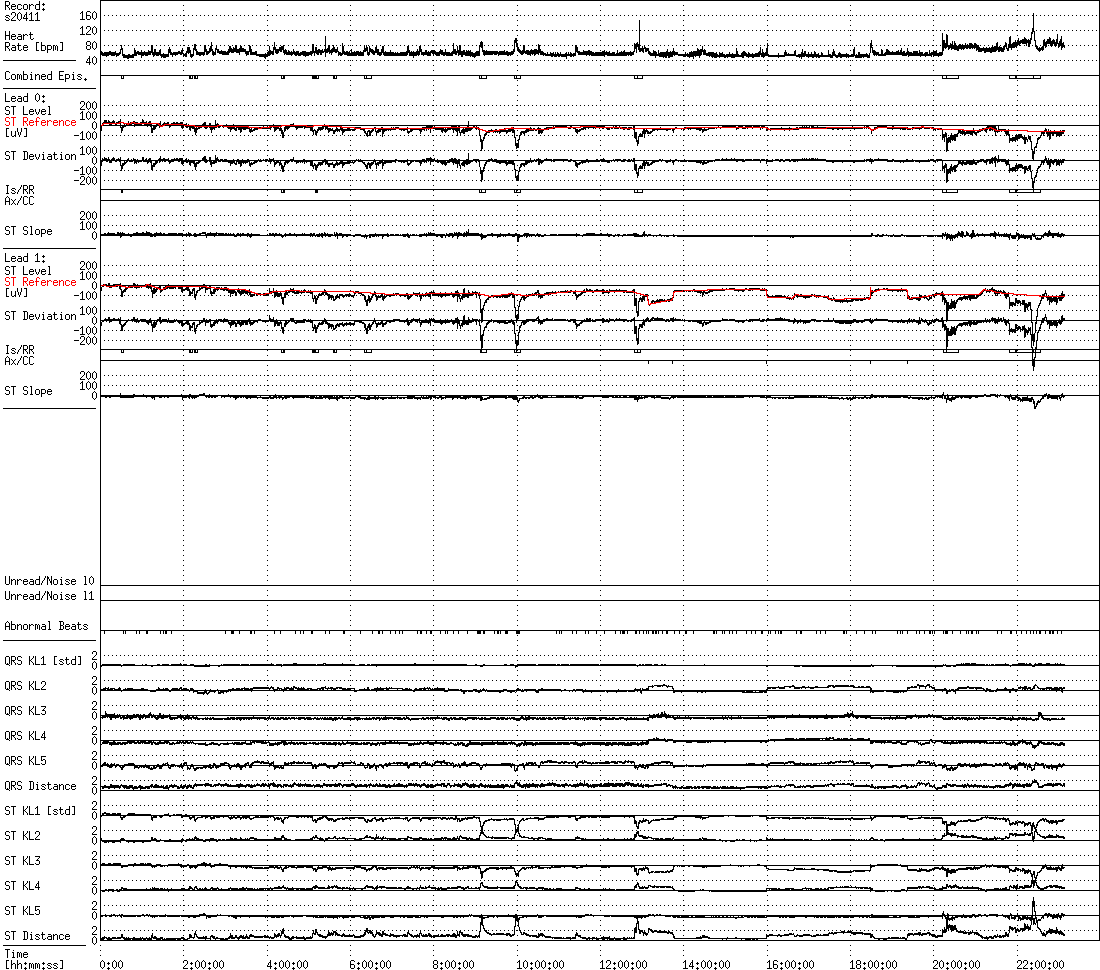

For each record, the numbers of ST episodes as determined by each of the three sets of criteria are summarized in an additional text file (with suffix .cnt). The deviation functions and the locations of the episodes are presented graphically in a set of trend plots here. Each record is represented by a 24-hour plot (_00-24.png) and by five 6-hour plots which overlap by one hour (_00-06.png, 05-11.png, etc.).

The first task faced by the expert annotators was to mark the locations of the PQ junction (the isoelectric level) and the J point, based on 16-second averaged cardiac cycles chosen at frequent intervals throughout the recordings. These marks serve as guideposts for the automated ST level measurement algorithm that performs the next step. The experts then examine the time series of ST level measurements in order to locate and to mark a set of local reference points (marked as LR in the upper panel of the figure). These are used to construct a piecewise linear baseline ST level function, which may vary over time as a result of body position changes or other factors unrelated to ischemia, especially in subjects with prior myocardial infarctions. Axis shifts reflect body position changes, and are usually most apparent in the QRS complexes (note the changes in the QRS principal components, KL1 - KL5, in the lower panel of the figure). By contrast, when ischemic ST changes occur, they are most apparent in the principal components of the ST segment (see the lower panel in this screenshot). Local references are placed before and after each such episode, and the episodes are annotated next. During this process, the expert annotators have the option of viewing either the ST level time series or the ST deviation time series (formed by subtracting the baseline ST level function from the uncorrected ST level time series), as shown in the upper panels of the two screenshots. For further details, see reference 4 below.